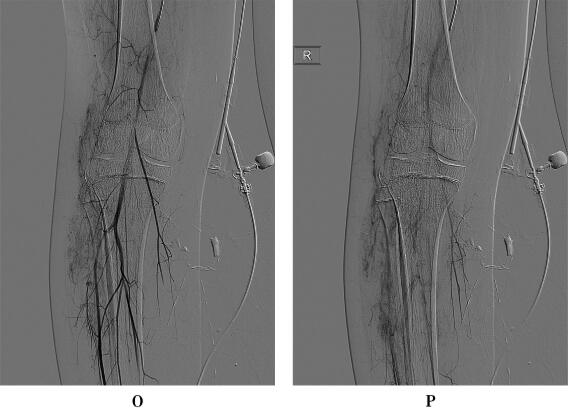

DSA经皮超选择性动脉造影:右膝、胫骨外侧动脉期可见增粗胫前动脉分支供血,动脉中末期上述部位可见畸形血管团,引流静脉进入腘、股静脉,证实为动静脉畸形,向畸形血管团内注入1.5ml无水酒精+0.5mPVA+博来霉素混合液行畸形血管栓塞治疗。

右侧膝关节、胫骨外侧软组织内动静脉畸形(AVM)。

动静脉畸形(AVM)是一种先天性发育异常,源于胚胎第4~8周局部血管异常分化,占血管瘤和血管畸形1.5%,男女比例为1∶1.5,可发生于身体任何部位,以中枢神经系统、头颈部、骨盆和下肢更常见,通常出生即存在,随身体发育同步缓慢生长,可长期稳定,也可突然迅速增大。在诊断上,普通CT或MRI平扫加增强扫描显示病灶为软组织肿块,缺乏特异性,难以与其他软组织肿瘤或肿瘤样病变鉴别,确诊依赖血管造影检查。DSA能准确显示AVM异常血管团的范围、供血动脉、引流静脉等信息,清晰显示各级血管及动静脉的异况,并能动态显示病灶血流动力学特点,空间和时间分辨力均高,还可同步进行血管内治疗,长期被认为仍是诊断AVM的“金标准”,但是DSA属于创伤性检查,X线辐射剂量较高、检查费高、不能显示病灶与周围组织的关系等诸多缺陷,逐渐被无创伤的血管成像所替代。其中CE-MRA是一种相对简便易行、无创伤、无射线辐射危害、价格相对便宜的诊断方法,当对比剂首次通过靶血管区,在峰值的一段时间内,从三维方向快速采集感兴趣区的图像数据,并通过各种后处理技术最终产生类似DSA的效果,并可获得多角度投影的CEMRA图像,CE-MRA可客观、准确评价下肢血管情况,清晰显示病灶范围及与周围软组织关系,并能区分不同类型血管畸形。AVM难以治愈,在治疗上,外科手术难度大,术后容易复发,目前倾向于多学科联合治疗,其中介入栓塞治疗是重要的治疗手段。本例病变位于右下肢软组织内,MRI平扫和增强扫描显示软组织肿块,缺乏诊断特异性,难以与各软组织良恶性肿瘤鉴别,CE-MRA显示典型的异常血管团、供血动脉和引流静脉,确定AVM的诊断,DSA进一步证实诊断并实施介入栓塞术。